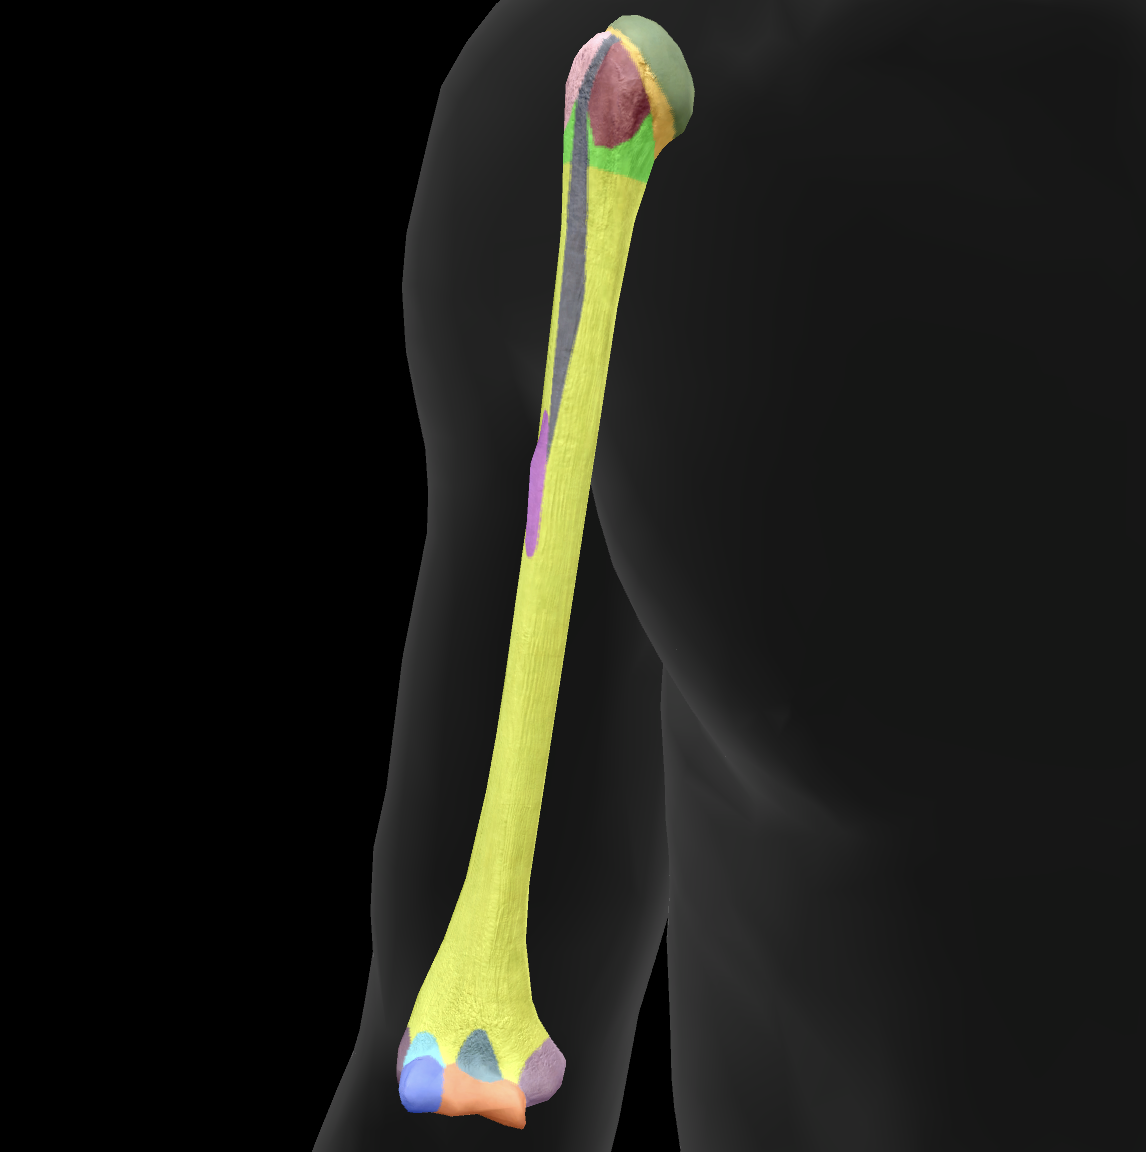

What bone is this?

ulna

What is this boney landmark?

trochlea notch

What is this boney landmark?

coronoid process

What is this boney landmark?

radial notch

What is this boney landmark?

ulnar tuberosity

What is this boney landmark?

shaft

What is this boney landmark?

head

What is this boney landmark?

styloid process

What is this boney landmark?

olecranon process

What is this bone?

radius

What is this boney landmark?

head

What is this boney landmark?

neck

What is this boney landmark?

radial tuberosity

What is this boney landmark?

shaft

What is this boney landmark?

radial styloid process

What is this boney landmark?

ulnar notch

What is this boney landmark?

lister’s tubercle